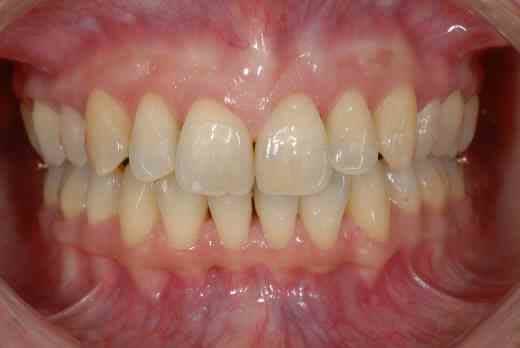

3 mois de mini vis et d'élastocs de classe II :-))

chuis pas belle comme ça? :-)))

heureusement le travail a été mené àson terme et le résultat final n'est pas mal, non?

la technique linguale est plus difficile à maîtriser, les points d'appui plus difficiles à trouver (cf minivis qui doivent rester esthétiques, c le but du traitement)